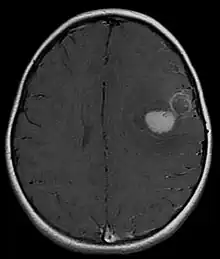

| Primitive neuroectodermal tumor of the central nervous system in a 5-year-old |

Several analysis can be used to determine the presence of the disease. Physical examinations showing papilledema, visual field defects, cranial nerves palsy, dysphasia, and focal neurological deficits are evidences for possible tumor.[2] PNETs can also be spotted through computed tomography (CT) and magnetic resonance imaging (MRI).[2] In images produced by MRIs, an irregular augmentation among a solid mass will indicated the presence of tumor.[3] However, the results of MRIs are usually ambiguous in defining the presence for this specific tumor.[2] In CT scans, the presence of PNETs will be indicated by an elevated density and an increase in volume of the brain.[2] The CT scan can also show calcification,[3] which is present in 41-44% of PNET cases.[2] Since the tumor can be replicated in other parts of the nervous system through the cerebrospinal fluid (CSF), a CSF analysis can also be conducted.[2] A spinal MRI is a fourth type of analysis that is useful in investigating the level of tumor propagation to the spinal cord.[2]